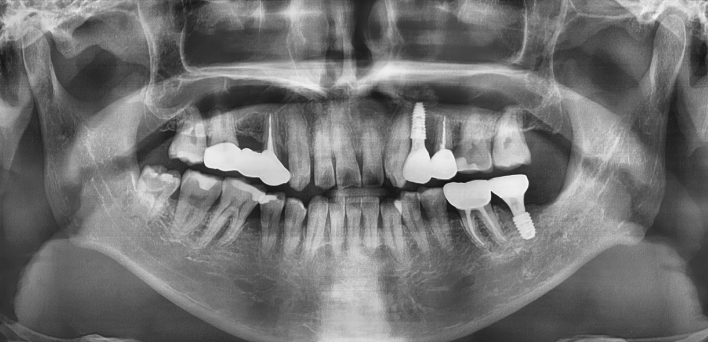

임플란트 : 손 ** 님 (50대)

치아가 있다는게, 아직도 정말 꿈만 같아요.

환자 특징

환자 특징01무치악 상태

환자 특징02수년간 무치악으로 지내심

임플란트가 불가능할것이라

생각하고 내원

위, 아래 6개씩 식립

디지털 풀아치 임플란트